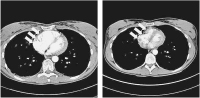

CT-Angiographie

Abbildung 1: CT-Angiographie mit bipulmonaler zentraler Lungenarterienembolie, als Kontrastmittel-Aussparung unter Betonung des Hauptstammes der linken Pulmonalarterie (Pfeile)